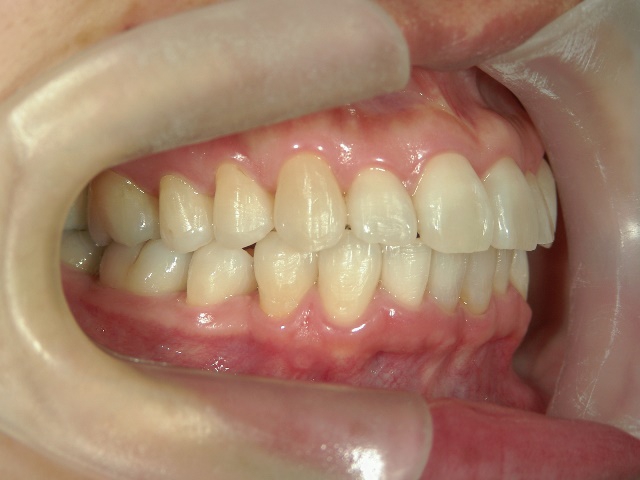

矯正歯科 治療後矯正歯科 プチワイヤー矯正 治療後矯正歯科(プチワイヤー矯正)治療後

no.41_8994_治療後_右.JPGno.41_8994_治療後_正面.JPGno.41_8994_治療後_左.JPG

矯正歯科 治療後 ミニインプラントを2本埋入し、下顎前歯を圧下